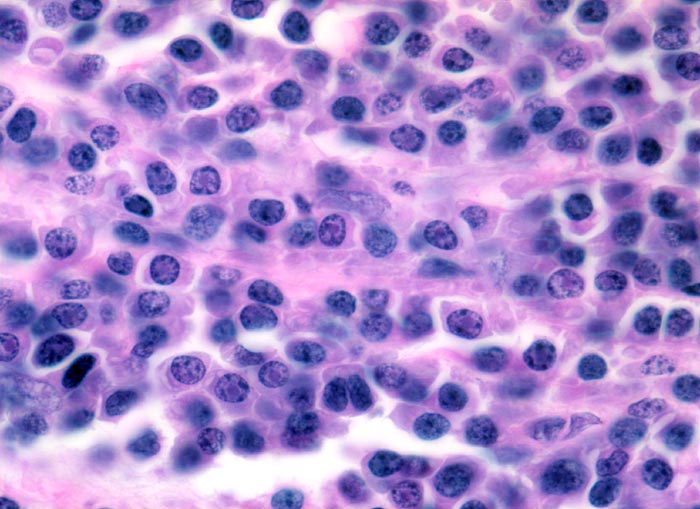

In dieser Giemsa-Färbung sind die Plasmazellen gut erkennbar. Die Plasmazellen sind polymorph, vereinzelt mehrkernig. Exzentrisch im Zytoplasma lokalisierte vergrösserte Radspeichenkerne . Reichlich violettes Zytoplasma mit paranukleärer Aufhellung. Zellkerne teils mit vergrössertem Nukleolus.